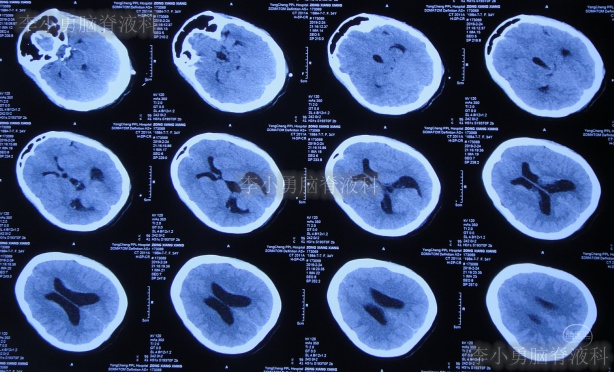

但腰椎穿刺术后头痛仅短暂缓解1天左右,在该院继续治疗8天,仍间断头痛发热,间断给予腰穿治疗,化验脑脊液白细胞高,曾先后3次查头颅CT(图-5、图-6、图-7)均示脑室并未明显扩张。

图-5:2019年2月26日头颅CT

图-6:2019年2月27日头颅CT

图-7:2019年3月5日头颅CT